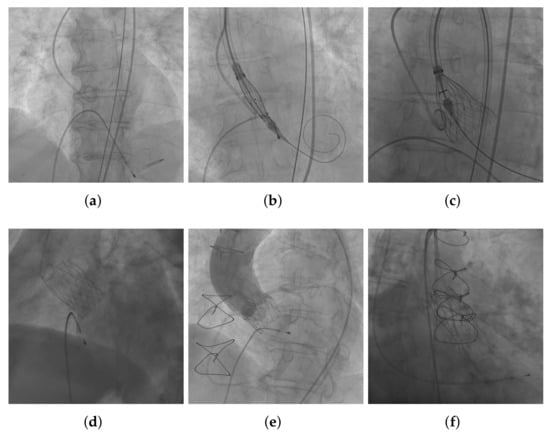

3.1. Image Acquisition and Annotation